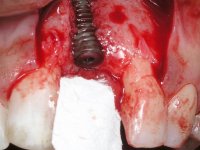

3) Colocação de um implante no espaço criado na zona do 21 associada a uma regeneração óssea guiada da zona,

4) Reabilitar prostodonticamente o implante com um coto de oxido de zirconio e uma coroa de cerâmica vítrea prensada de dissilicato de lítio no sentido de obter o resultado estético pretendido.